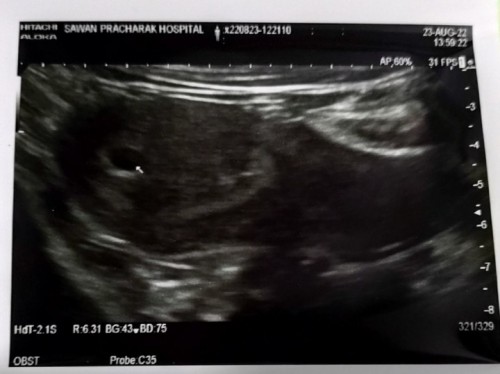

มีแม่ท่านไหนไปอัลตร้าซาวด์แล้วถุงตั้งครรภ์เล็กไม่สัมพันกับอายุครรภ์บ้างคะจากที่หมอคำนวนจากประจำเดือนครั้งสุดท้ายอายุครรภ์ได้10 wแต่พอซาวด์เจอถุงตั้งครรภ์แค่0.63 mm. ยังไม่เจอตัวอ่อนหมอนัดซาวด์อีกที3สัปดาห์ตอนนี้กังวลมากค่ะ😔

ซาวด์เมื่อ30ส.คอายุครรภ์พึ่งได้4w4dอีก1เดือนหมอนัดซาวใหม่ค่ะลุ้นมากๆ